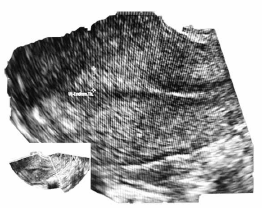

C.V.R.S., 36 anos, G VII P VI (6N) A0, IG cr: 6 semanas,deu entrada no PSGO com sangramento vaginal há cerca de 1 semana. Sem ultrassom prévio. Ao exame físico: especular: colo uterino sem lesões, mínima quantidade de sangue vermelho escuro em fórnice posterior. TV (toque vaginal) bimanual: colo impérvio, grosso, posterior. Ausência de dor à mobilização do colo uterino. Abdome: DB negativo, dor leve à palpação profunda de hipogástrio. Submetida à ultrassonografia transvaginal (imagens a seguir: figuras 1, 2, 3, 4) e beta HCG quantitativo: 9 000 UI/mL. Resultado de beta HCG 24h antes: 7 000 UI/mL.

Figura 1 (útero; EE 5 mm)